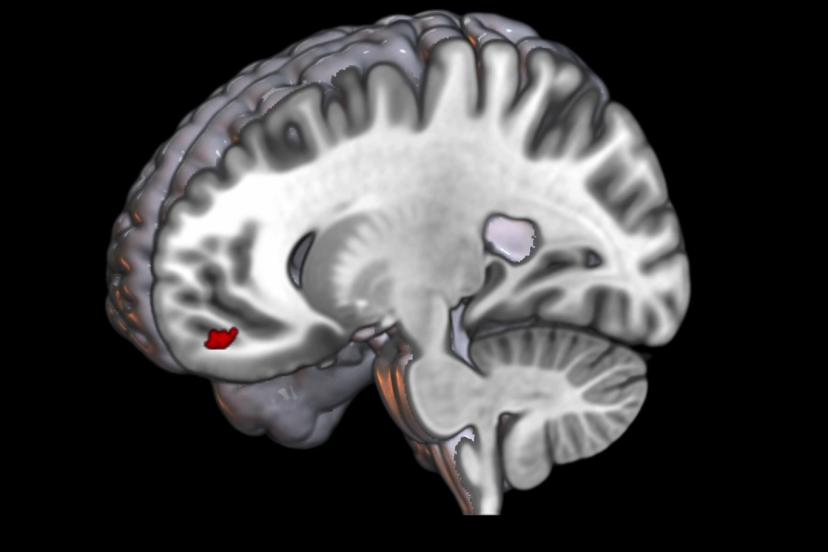

“Normal insan beyninde tekrarlayan uyarı geldiğinde beyin buna verdiği tepkiyi azaltıyor. Ama migrenli beyin aksine tepkiyi giderek arttırmaya başlıyor.” diyen Prof. Dr. Belen, bu artışın, görsel işlemenin yapıldığı beynin arka kısmında değil aksine beynin en ön kısmında bulunan ve üst düzey kontrol merkezi olan orbitofrontal bölgede gerçekleşmesinin son derece önemli olduğunu ifade etti. Belen, “Burası görmenin üst düzey kontrol merkezi ve aynı zamanda da gelen uyarıya zararlı, faydalı ya da duygusal bir değer biçen yer.” dedi.

Doktora sonrası araştırmacı Dr. İlkem Güzel de “Alt düzey görsel işlemleme bölgelerinin doğrudan ağrı bölgesiyle ilişki halinde olduğunu tespit ettik. Bu tespit bize migren hastalarında ışıktan rahatsız olma durumunu açıklama fırsatı sundu.” dedi.